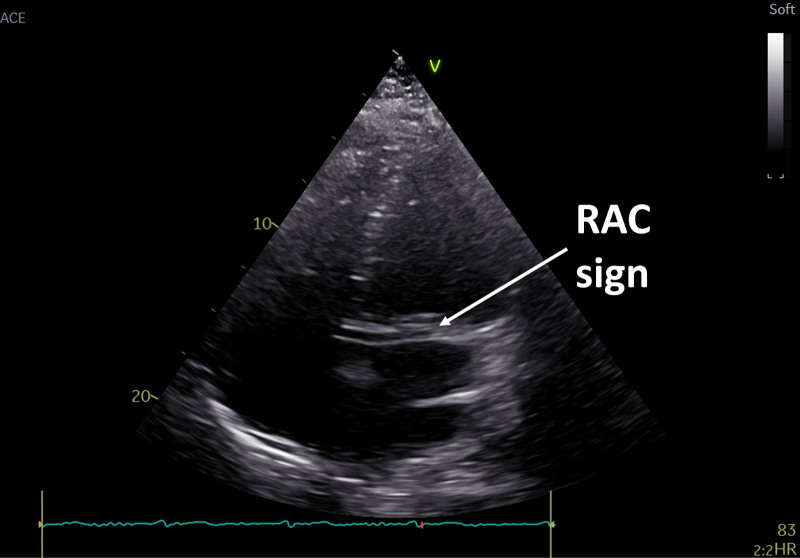

All coronary arteries originating from the right sinus of Valsalva: a multimodality imaging approach.